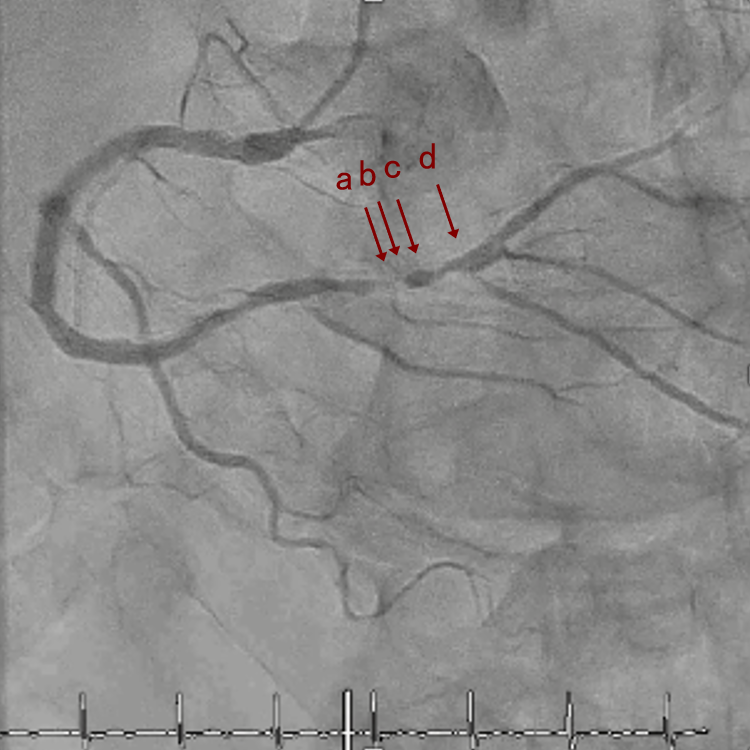

PreのIVUSではaの部位のみlipid plaqueを認め削ることでdistal embolismのリスクがあり、そのほかは270度の偏心性石灰化であるがwire biasは良好。

OAS low speedによる引きを赤線の区間行う方針とした。

OAS low speedによる引きのsandingを3回行いIVUSを確認するとa-cでは心筋側側へのOASによる良好なbias変化と、それに伴いdの健常側への危険なbias変化を認めた。

そのためcでIVUSマーキングを行い、その点より引きで赤線のpinpoint OAS high speedを行い、dに関してはinjury回避のためにOASを当てない方針とした。